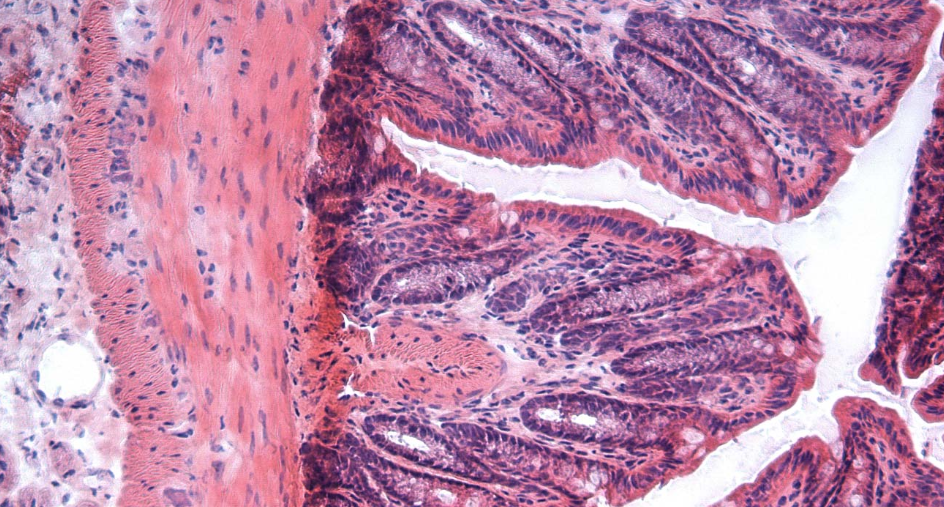

Dextran sulfate sodium for colitis (DSS)

Dextran sulfate sodium (DSS) is the goldened standard for inducing colitis in experimental animals.

DSS is a dextran sulfate with a mean molecular with of 40 kDa and a sulfur content of 17-19 %.

About 40 years ago, TdB Labs was involved in the work that led to the development of colitis-grade DSS.